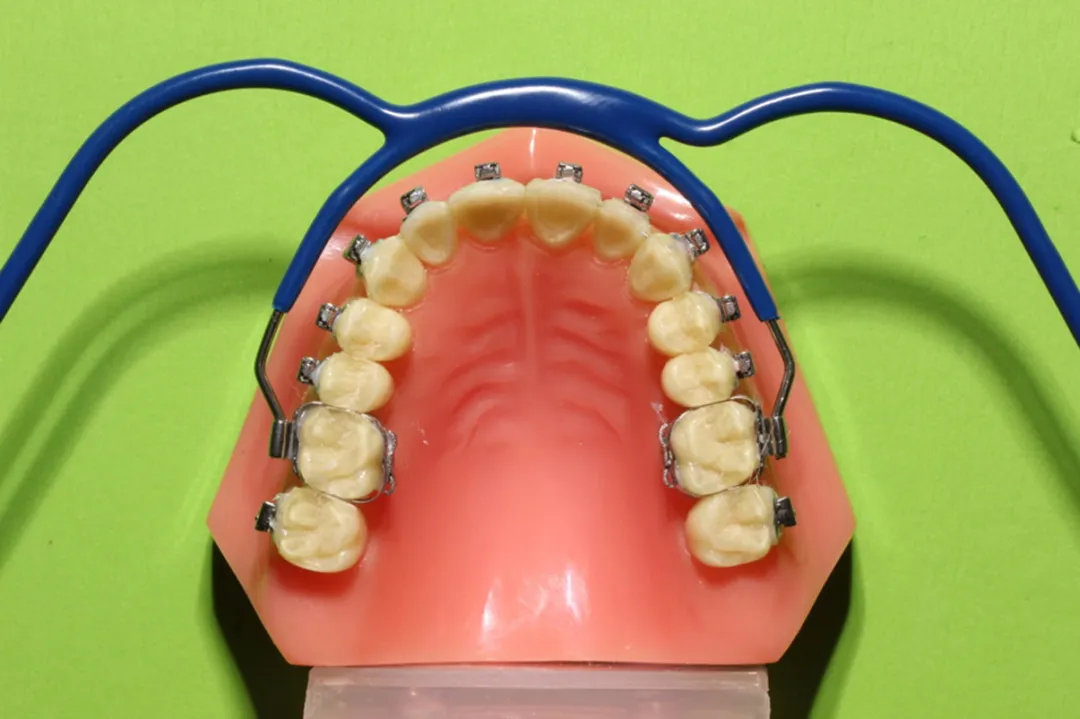

牙齿矫正过程中,在年轻恒牙列也会用到头帽肌激动器,因为有些孩子排齐的时候,需要给他往后收,尤其是无托槽隐形矫正过程中,这个时候孩子7号牙还没萌出,只是6号牙萌出,且这时候骨骼结构比较软,打骨钉骨头比较软容易松动脱落,孩子也比较难受,所以这个时候用头帽肌激动器可以防止排齐过程中出现前牙唇倾。